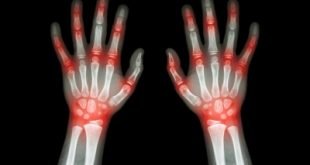

5 Hal Krusial dalam Konseling Tentang Asam Urat Untuk Para Apoteker

Farmasetika.com – 6/6/2016. Banyak pasien yang menderita asam urat atau gout akan mencari bantuan ke klinik atau apotek terdekat untuk meredakan nyeri. Beberapa penelitian menunjukkan bahwa prevalensi penyakit ini terus meningkat. Menurut survei WHO, Indonesia merupakan negara terbesar ke 4 didunia yang penduduknya menderita asam urat dan berdasarkan sumber dariBuletin Natural, di …